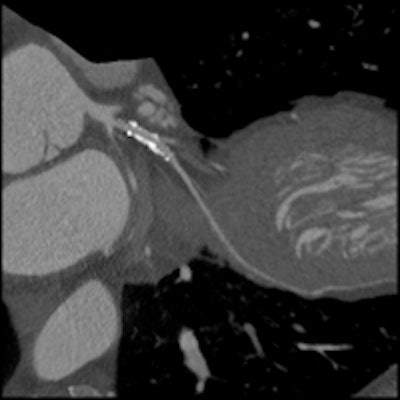

Image series shows comparison images demonstrating how high-definition CTA improved reporting accuracy. Case is a 49-year-old man with previous stent to the circumflex artery with recurrent pain. Left: Image shows a stent in the circumflex artery but no stenosis. Right: Image shows an occluded right coronary. All images courtesy of Dr. Carl Roobottom."My analogy would be a conventional detector is like an energy-saving light bulb, so we turn it on and off very quickly, [and] you still get some light in the background, whereas the gemstone is a bit more like a flashlight so acts like a strobe," he said.